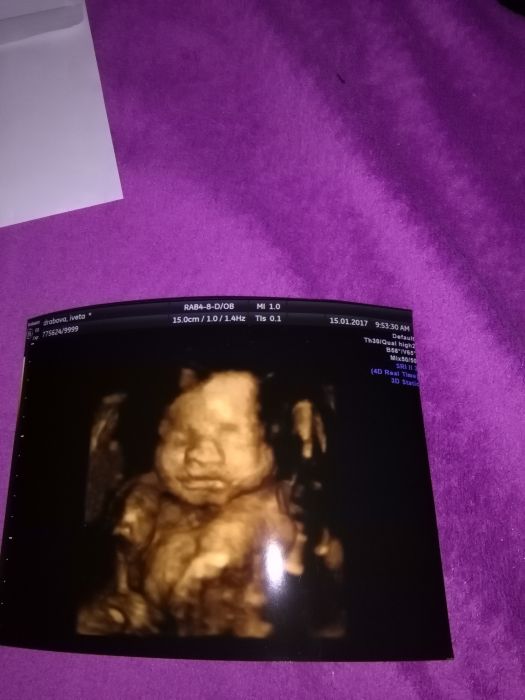

3D jinak neukazala nic před obličejem měla obě nožičky a ruku zahlavou .